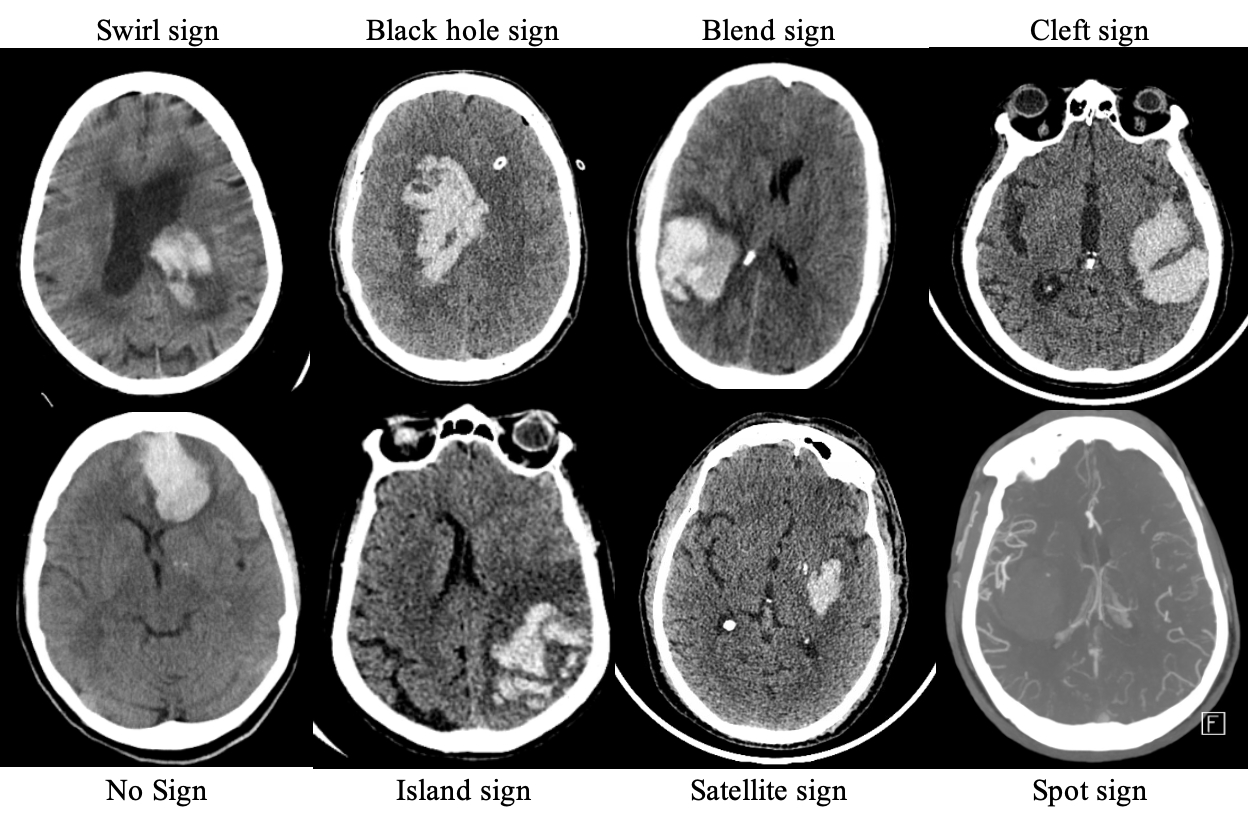

Methods: This study included all patients presenting with ICH who underwent MIS ICH evacuation from 2016 to 2021. The presence of spot sign, swirl sign, blend sign, black hole sign, satellite sign, island sign, and cleft was identified on pre-operative CT imaging. Univariate and multivariate analyses were performed between CT markers and variables of operative outcome with R v 4.3.1.

Results: 221 patients met the inclusion criteria. Swirl sign was identified in 127 patients (57%), spot sign in 30 (14%), black hole sign in 60 (27%), island sign in 10 (5%), satellite sign in 63 (29%), blend sign in 32 (14%), and cleft in 59 (27%). On univariate analysis, presence of any hematoma characteristic was correlated with increased intracavitary bleeding score (2.61±1.35 vs. 2.00±1.94, p = 0.027). Spot sign was correlated with increased rate of surgical rebleed (3.7% vs 2.4%, p = 0.021). Satellite sign was correlated with increased rate of surgical rebleed (6.7% vs. 0.7%, p = 0.021) and marginally significant increased residual volume (12±17 mL vs. 8±11 mL, p = 0.066). Presence of a cleft within hematoma was correlated with decreased evacuation rate (0.76±0.21 vs. 0.85±0.2, p = 0.005), increased intracavitary bleeding score (3.03±1.44 vs. 2.39±1.22, p = 0.019), increased residual volume (14±13 vs. 7±12, p = 0.001), increased presence of amyloid (31% vs 17%, p = 0.034). Multivariate linear regression analysis of presence of cleft controlling for pre-operative hematoma volume predicted increased bleeding score by 0.56 (p = 0.026), and on separate analysis predicted decreased evacuation rate by 9% (p = 0.005). Multivariate ordinal regression analysis of presence of cleft controlling for pre-operative hematoma volume predicted increased probability of increased bleeding by 117% (OR 2.17, CI: 1.09 - 4.39, p = 0.029).

Conclusions: Preoperative hematoma heterogeneity, specifically presence of cleft, is associated with increased intracavitary bleeding, decreased evacuation rate and increased residual volume following MIS ICH evacuation. Understanding the impact of hematoma characteristics is integral for patient selection in MIS ICH evacuation and postoperative care planning.